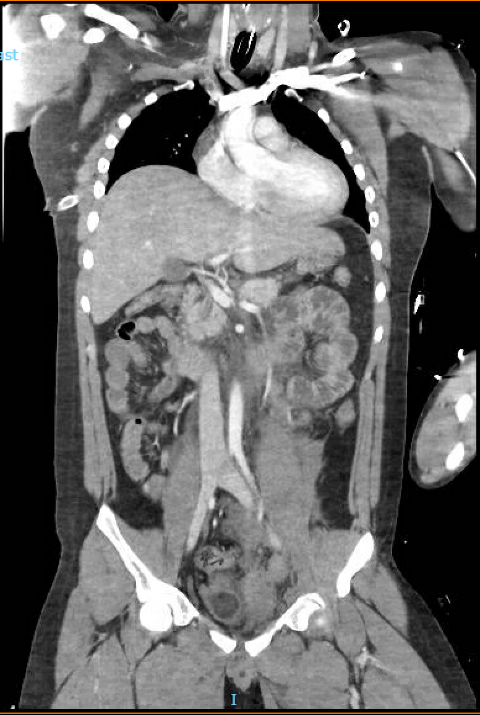

In the ED, a chest X-ray and a FAST scan were conducted, showcasing a small right hemothorax and no free fluid in the peritoneal or pericardial cavities, respectively. Following stabilization, a Computed Tomography (CT) of the Chest, Abdomen, and Pelvis was ordered ([Figure 1]), highlighting the following:

A small right pleural effusion with adjacent right lower lobe atelectasis, with a trace right pneumothorax.

Trace of left pleural effusion with adjacent left lower lobe atelectasis.

Non-enhancement of the entire left kidney on arterial and venous phases of imaging concerning for traumatic occlusion of the left renal artery.

Moderate-to-large left retroperitoneal hematoma extending inferiorly into the left hemipelvis along the course of the iliac vessels.

Small 1.9 × 0.9 cm contusion of the upper pole of the right kidney.

Displaced fractures of the left L1–L5 transverse processes and a mildly displaced fracture of the right L5 transverse process.

Minor fractures of the left inferior pubic ramus and upper left sacrum, with a widening of the left sacroiliac joint measuring 1.1 cm.

Small-to-moderate contained subcutaneous soft tissue hematoma overlying the lumbar spine.

The liver, gallbladder, bile ducts, heart, lymph nodes, and thyroid were unremarkable.